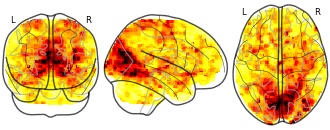

"description": "Multi-modal analysis in BPD. Brain regions exhibiting greater gray matter and enhanced activation during emotion processing in BPD compared to healthy controls. Note: Results were thresholded at p<.0025. Note2: Results were updated (see Erratum for this publication).",